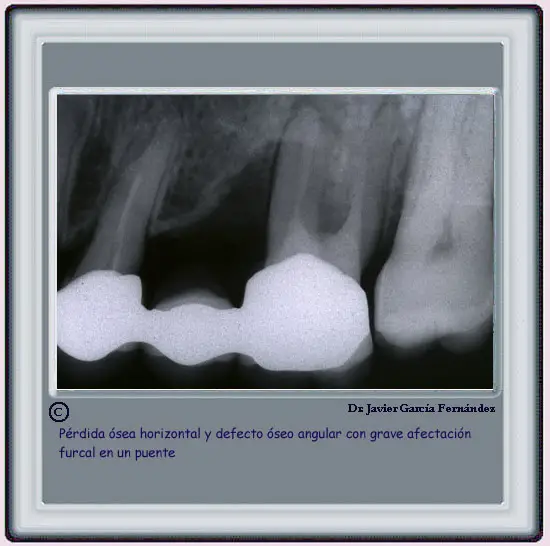

image244